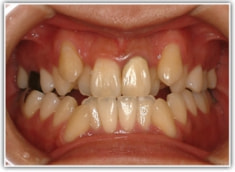

治療後(2年3ヶ月後)

骨格的な下顎前突の傾向は強くはありませんが、歯牙の状態によって反対咬合が認められます。LowTongue(低位舌)もあります。